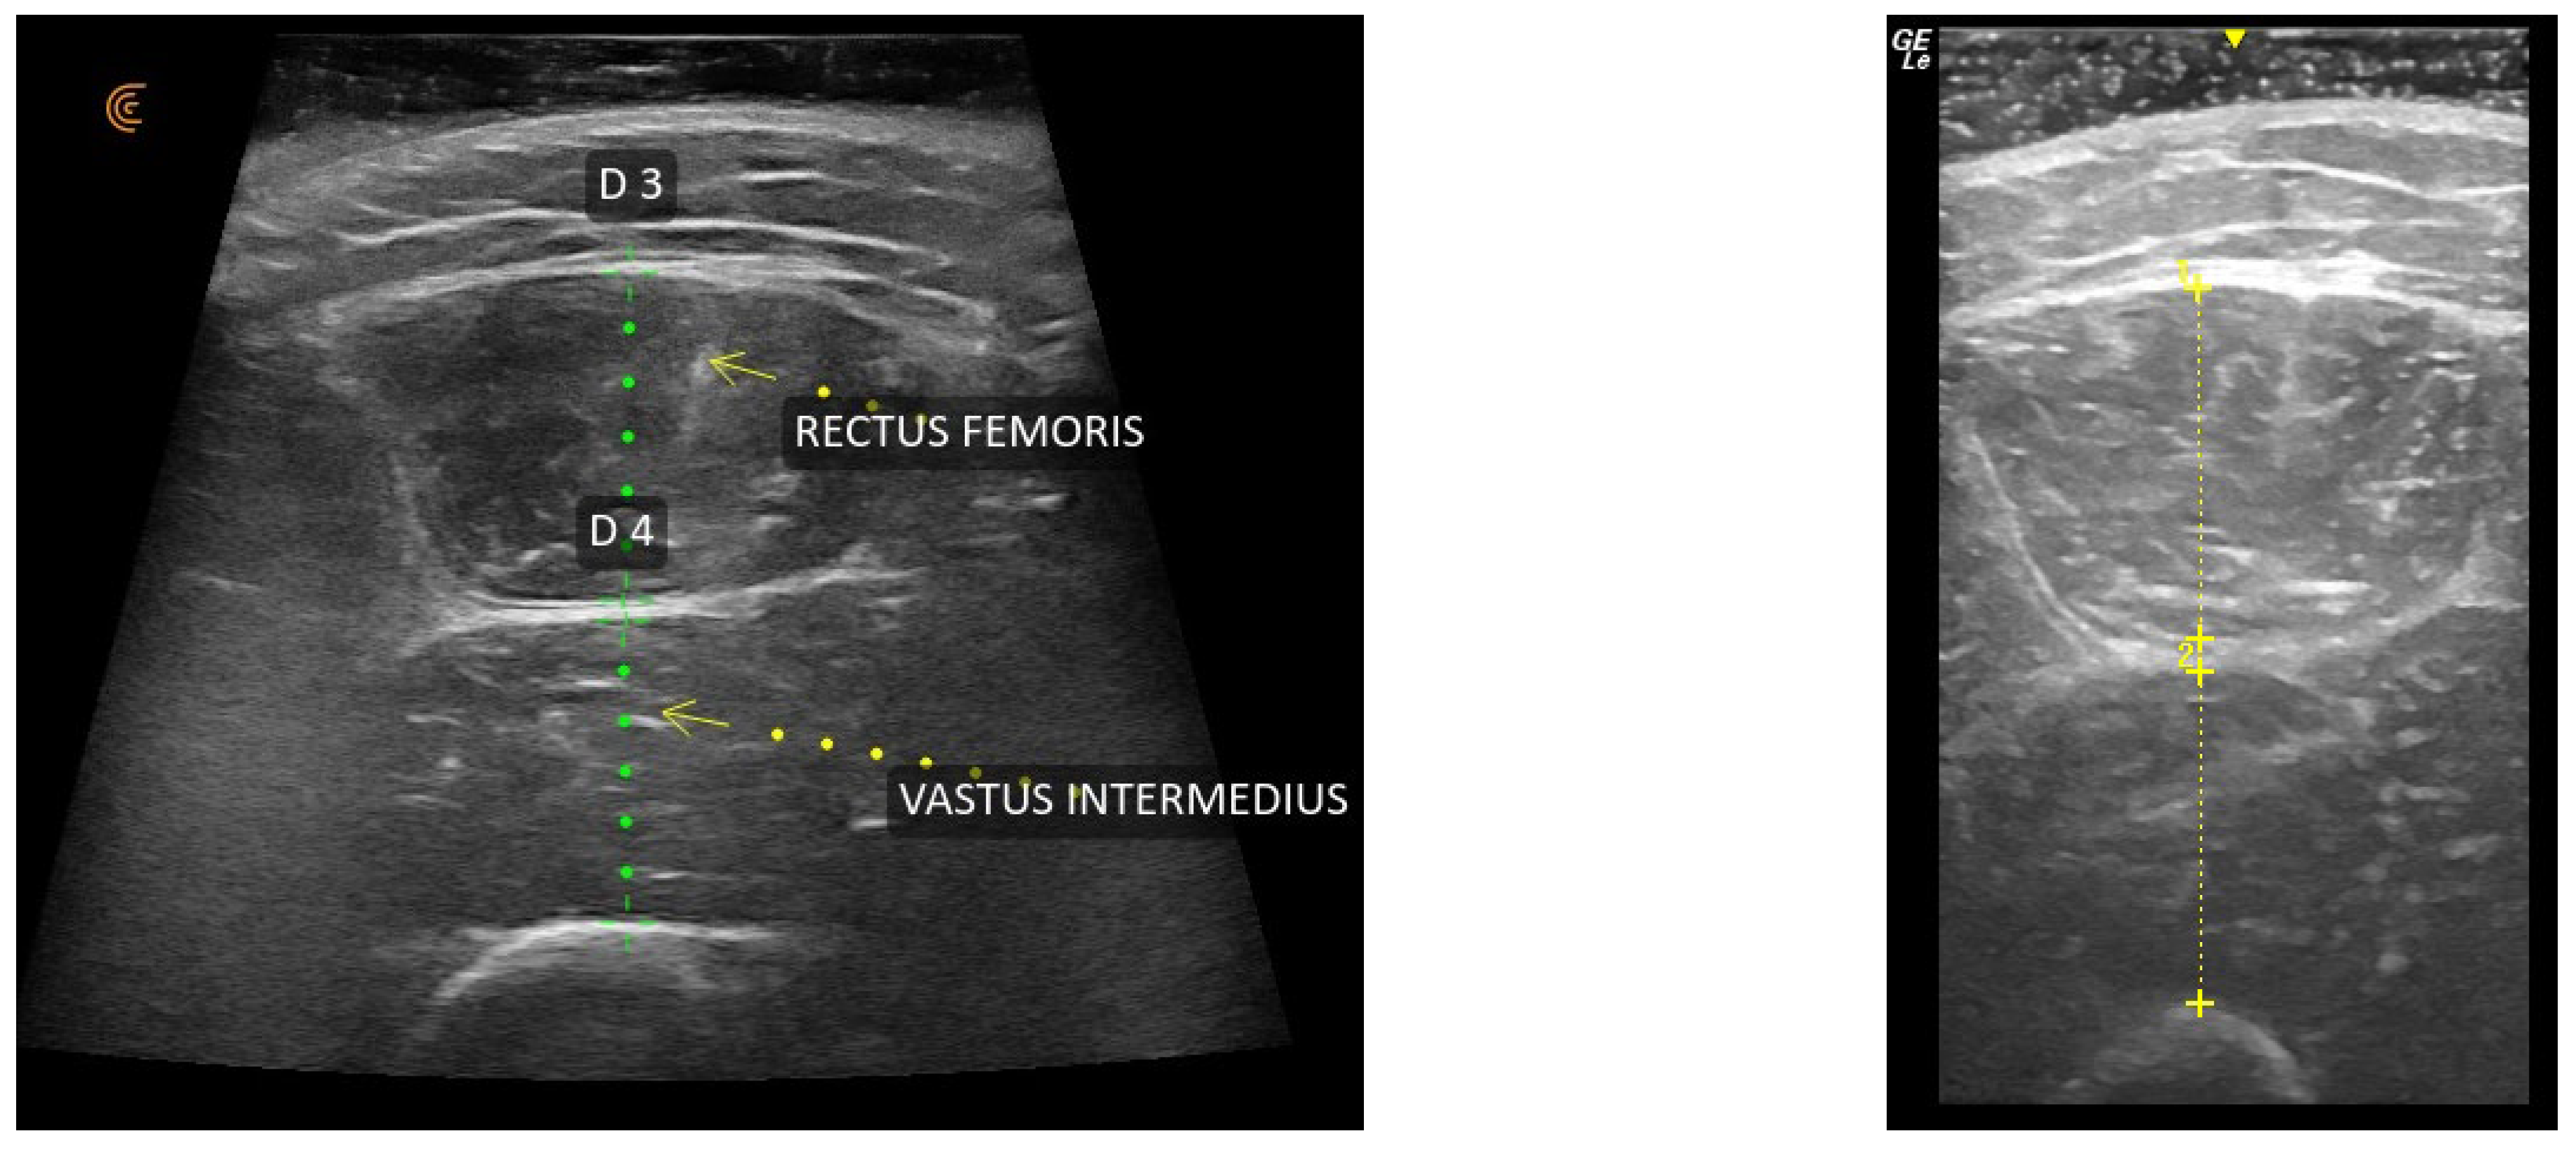

2.4. Ultrasound Assessment and Muscle Thickness Measurement